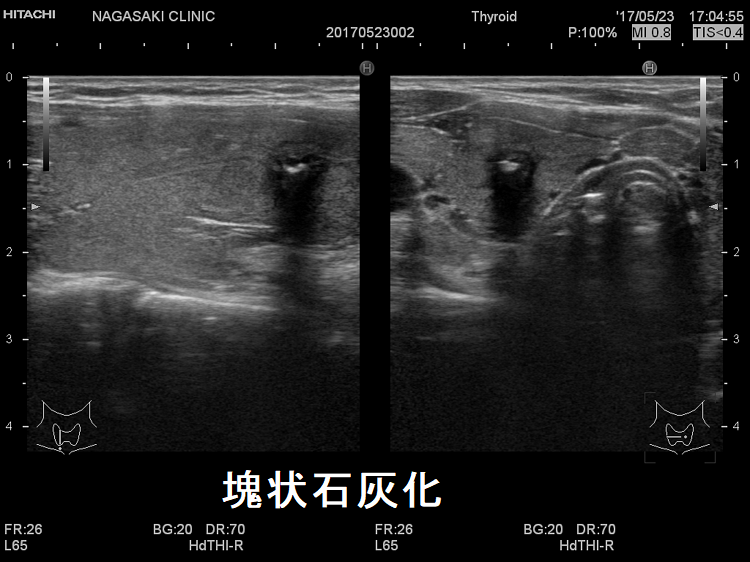

- 1cm以上の甲状腺乳頭癌と甲状腺微小乳頭癌で、石灰化率に有意差はないとされます[Exp Ther Med. 2014 Oct;8(4):1335-1339.]。しかし、甲状腺微小乳頭癌の石灰化パターンは、1cm以上の甲状腺乳頭癌とやや異なります。微細石灰化・斑点状石灰化・卵殻状石灰化の頻度は1cm以上の甲状腺乳頭癌と同じですが、甲状腺微小乳頭癌では破片状・塊状石灰化の頻度が多い。

ここで要注意なのは、超音波(エコー)装置の性能によって甲状腺の石灰化の見え方が変わる事です。解像度が低い超音波(エコー)装置(アナログ式のもの)では、微細石灰化の集団が粗大石灰化の様に見えます。一方、解像度が高い超音波(エコー)装置(プレミアム超音波診断装置、デジタルハイビジョン超音波診断装置)では、微細石灰化の音響陰影(acoustic shadow、アコースティック シャドウ)を伴わな い事が多く、壊死組織の様な高エコースポットに見えます。